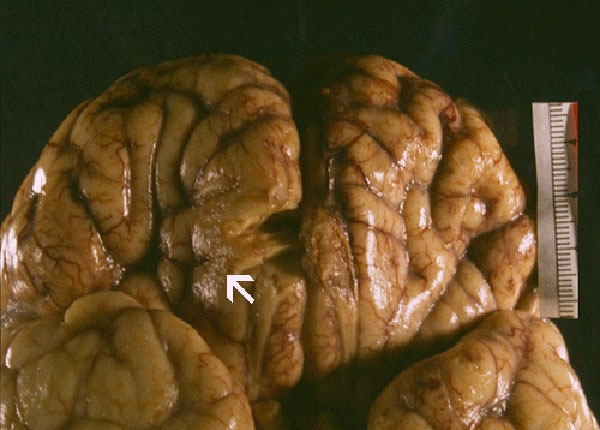

Ký sinh trùng ăn não

Là một loài sinh vật đơn bào, Naegleria fowleri được mệnh danh là “amip ăn não”bởi tác hại kinh khủng của nó một khi xâm nhập được vào trong cơ thể người. Dù hiếm khi xảy ra nhưng một khi N.fowleri đã xâm nhập được vào hệ thống thần kinh, người bệnh luôn phải chuẩn bị tinh thần đón nhận cái chết.

Ký sinh trùng ăn não là 1 trong những khám phá thế giới nguy hiểm nhất cho con người

Thông thường, Naegleria fowleri xâm nhập vào cơ thể con người qua đường mũi, sau đó sẽ di chuyển theo các sợi thần kinh khứu giác thông qua sàn sọ để lên não. Naegleria fowleri được cho là nguyên nhân gây ra căn bệnh viêm màng não với tỉ lệ tử vong lên đến 98%.

Người bệnh khó có cơ hội sống sót khi bị loài ký sinh trùng này xâm nhập

Loài “amip ăn não” này sinh sôi rất nhanh. Chúng ăn các nơron thần kinh, gây cho bệnh nhân những cơn đau đầu khủng khiếp, các cơn sốt cao, chứng ảo giác và thậm chí khiến người bệnh mất khả năng kiểm soát hành vi. Các nhà khoa học miêu tả mức độ nguy hiểm của chúng là: dẫn đến cái chết nhanh chóng đến nỗi rất khó nghiên cứu chúng tại phòng thí nghiệm.